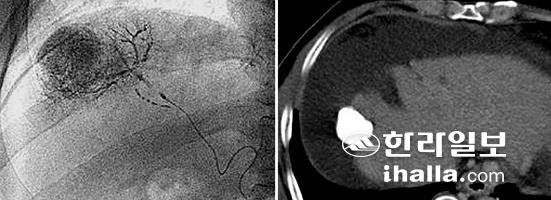

▲간세포암 환자에게 간동맥화학색전술 치료를 하는 동안 촬영한 혈관촬영기 X-ray 영상(왼쪽)에서 미세카테터를 통해 간세포암에 주입되고 있는 항암제와 리피오돌 혼합액이 잘 보이고 있다. 치료 6개월 후의 CT 영상(오른쪽)에서 간세포암에 새하얗게 잘 침착된 리피오돌이 계속 남아 있는 모습이 보여 간세포암은 재발 없이 완전히 치료됐다. 사진=제주대학교병원 제공

이미 진행된 간세포암의 치료에는 간동맥화학색전술이 가장 널리 이용된다. 인터벤션 영상의학에서 시행하는 혈관촬영술을 이용해 간세포암에 산소와 영양을 공급하는 영양동맥을 찾아 항암제를 투여한 후 영양동맥을 막아 혈류를 차단함으로써 암을 괴사시키는 치료법이다. 이렇게 간의 혈류를 차단해도 정상 간조직은 손상이 적고 암조직만 괴사하는 이유는 간이 간동맥과 문맥이라는 두 개의 혈관에 의해 혈액공급을 받기 때문이다.

정상 간조직은 주로 문맥에서, 간세포암은 주로 간동맥에서 혈액공급을 받기 때문에 영양동맥인 간동맥분지를 카테터로 선택해 항암제를 주입하고 혈관을 막게 되면 정상 간조직을 크게 손상시키지 않으면서 암덩어리만을 선택적으로 괴사시킬수 있다.

간동맥화학색전술은 이미 진행된 간세포암 환자의 생존율을 증가시킬 수 있는 치료법으로 입증됐으며, 현재 동맥을 막기 위해 사용하는 색전물질을 새로 개발하고 치료법을 향상시켜 보다 더 부작용이 적은 치료법으로 발전시켜 나가고 있다.